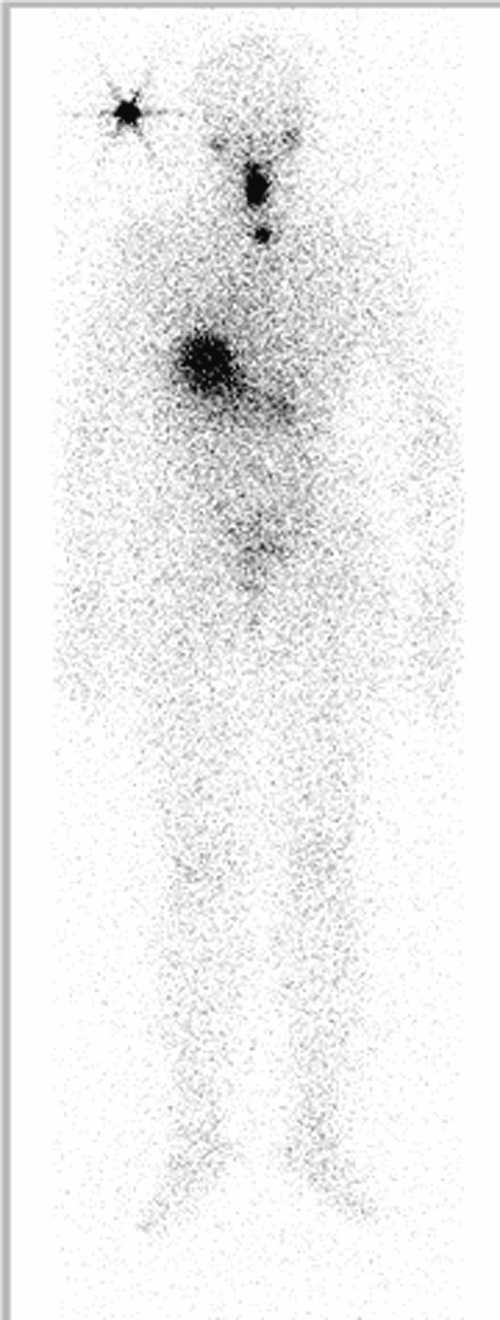

Um nach der Entfernung der Schilddrüse möglicherweise verbliebenes Gewebe vollständig zu entfernen, folgt bei Krebspatienten meist eine Radiojodtherapie. Radioaktives Jod, das in Kapselform eingenommen wird, wandert dabei in das verbliebene Drüsengewebe und zerstört es durch seine Strahlung. Vor einer solchen Therapie durften Patienten bisher keine Ersatzhormone einnehmen, denn unter dem - für die Patienten sehr unangenehmen - Hormonentzug bildet der Körper einen Stoff (TSH = schilddrüsenstimulierendes Hormon), der die Radiojodtherapie erst möglich macht. Wie die Erfolge mit synthetisch hergestelltem TSH sind, das den Patienten gespritzt wird, so dass ein Hormonentzug nicht notwendig ist, darüber klärt Prof. Dr. Markus Luster, Leitender Oberarzt der Ulmer Universitätsklinik für Nuklearmedizin, auf.